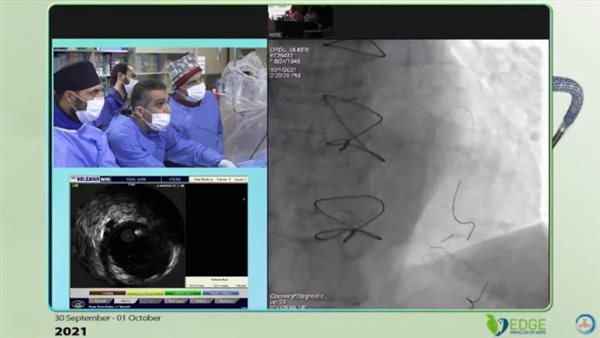

أعلنت الهيئة العامة للرعاية الصحية، عن نجاح رئيس قسم القلب بمستشفى النصر التخصصي للأطفال التابعة للهيئة بمحافظة بورسعيد الدكتور طارق رشيد، في إجراء قسطرة قلبية معقدة لعلاج إحدى الحالات المرضية بمستشفى ميموريال Memorial Hospital في مدينة إسطنبول بدولة تركيا.

وأضافت الهيئة، أنه جاء ذلك خلال مشاركة استشاري القلب الدكتور طارق رشيد في مؤتمر للقسطرة التداخلية المعقدة بمدينة إسطنبول في تركيا، لافتة إلى أن الهدف الرئيسي من إجراء هذه العملية هو تبادل الخبرات بين مصر وتركيا في مجال معالجة أمراض القلب باستخدام القساطر التشخيصية أو العلاجية كأحدث التقنيات العلاجية وفق ممارسات الصحة العالمية.

وقال الدكتور طارق رشيد، استشاري القلب والقسطرة وعضو هيئة التدريس بكلية الطب جامعة عين شمس ورئيس قسم القلب بمستشفى النصر التخصصي للأطفال ببورسعيد، أن الهدف الرئيسي من إجراء هذه العملية في مستشفى ميموريال بإسطنبول تركيا هو نقل المعرفة والعلم والخبرات التي اكتسبها على مدار سنوات عمله الممتدة لعلاج أمراض القلب وفق أحدث الإرشادات والبروتوكولات العلاجية المعتمدة دوليًا إلى الكوادر الطبية التركية وتدريبهم على إجراء مثل تلك العمليات النادرة، مؤكدًا أن الأطباء المصريين لا يقلون كفاءة عن نظرائهم في دول العالم المتقدمة طبيًا.